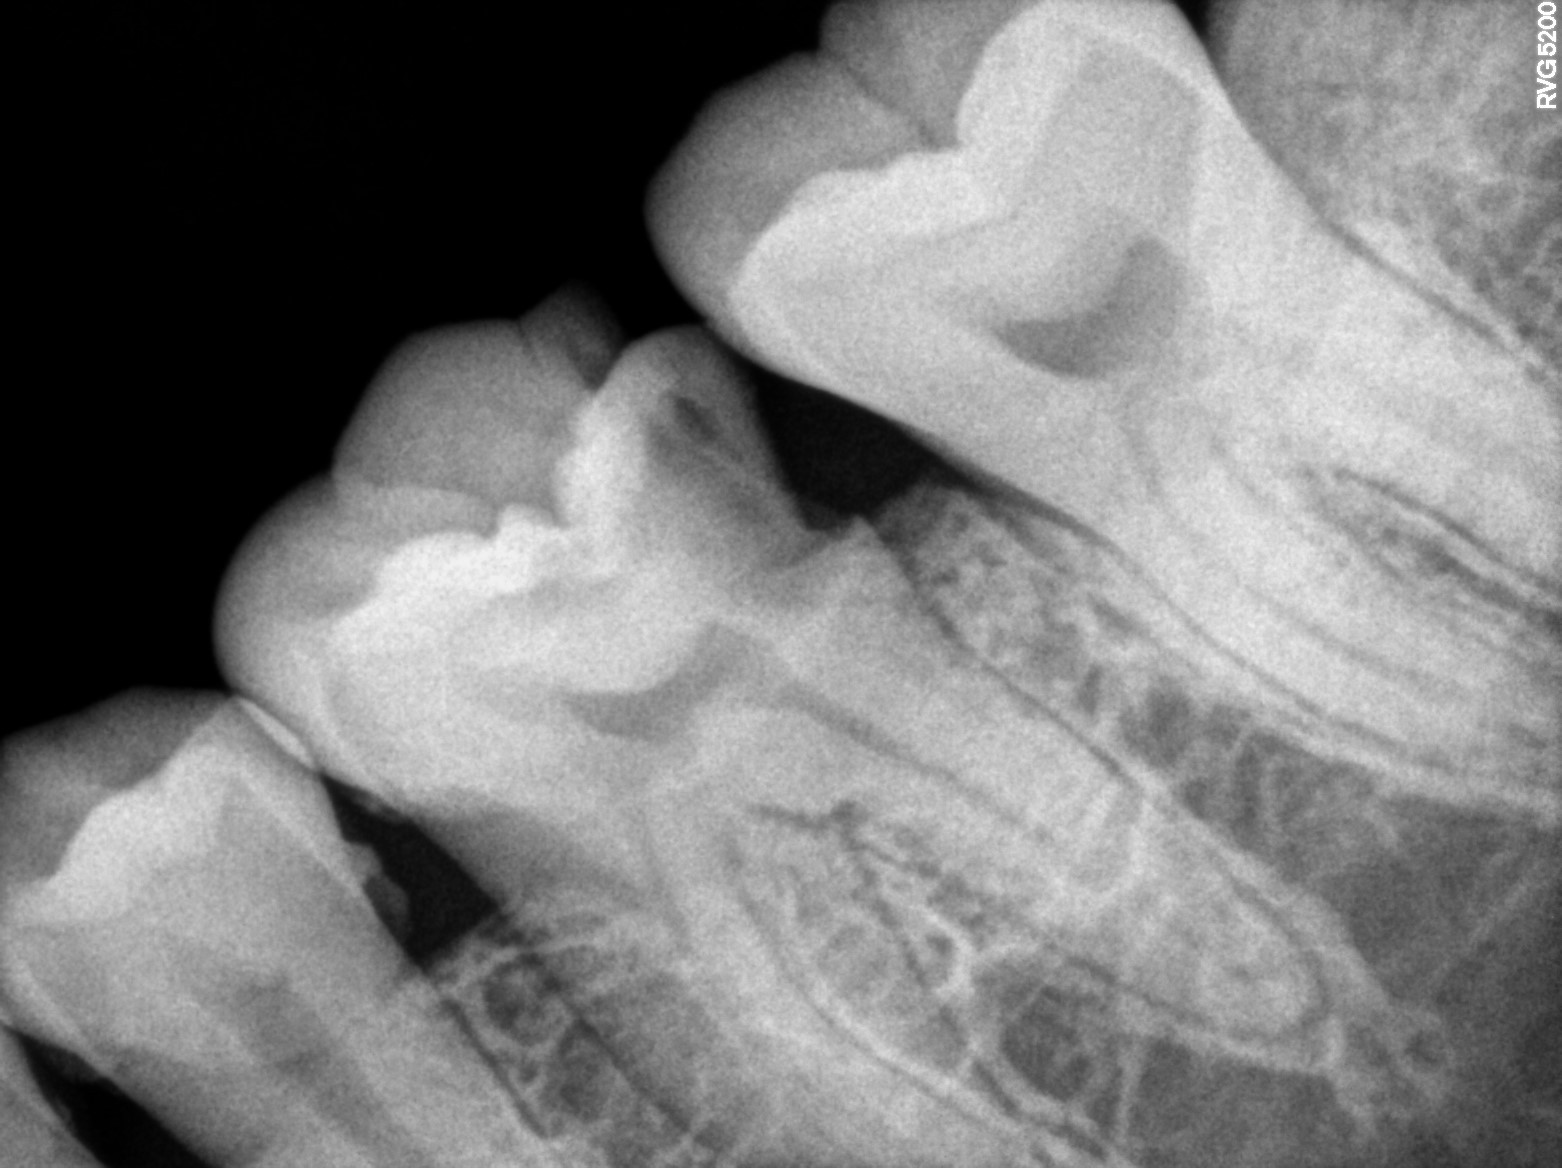

Dental Radiographs FHIR: DocumentReference · LOINC 24641-7

xray_1766483090_1.jpg

24641-7

xray_1766483090_0.jpg